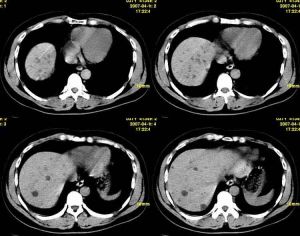

其他檢查常規行雙腎B超檢查,酌情作CT檢查、靜脈腎盂造影或逆行尿路造影,必要時可行腎核素掃描、骨髓穿刺檢查及腎組織活檢。

③早期腎小管功能受損為主(見急性間質性腎炎),晚期內生肌酐清除率下降,血中尿素氮及肌酐升高。如系止痛藥性腎病,逆行造影可見腎乳頭壞死特徵;如系慢性腎盂腎炎,腎CT或B超檢查可見雙腎外形不規則、腎盂、腎盞變形。